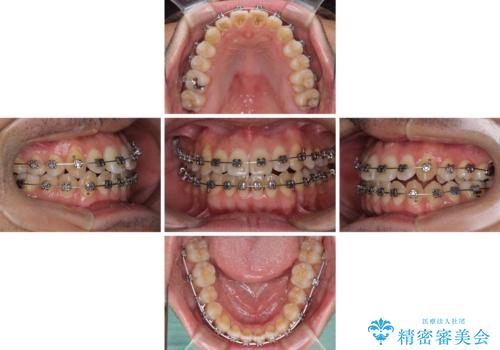

- 矯正装置

- メタルブラケット

- 治療期間

- 4年1ヶ月

- 治療回数

- 10-30回

舌の突出癖がなかなか改善されず、上下前歯部の接触が得られるまでに予定の倍ほどの期間がかかりました。